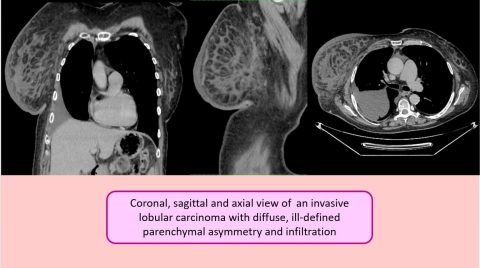

Invasive Breast Carcinomas: 3 interesting cases

Histopathological analysis ultimately revealed two cases of invasive ductal carcinoma (IDC) and one case of invasive lobular carcinoma (ILC), representing the most common and second most common subtypes of invasive breast malignancy, respectively.

The patient with invasive lobular carcinoma demonstrated more subtle imaging features, with diffuse, ill‑defined parenchymal asymmetry and infiltration rather than a well‑circumscribed mass. This pattern is characteristic of the infiltrative “single‑file” growth of lobular carcinoma, which can be more difficult to recognize on imaging compared to ductal carcinoma. No distant metastases were identified in this case at the time of detection.

Fig 4.jpg

CT and Histology Highlights:

• ILC: diffuse breast parenchymal asymmetry and infiltration, no discrete mass, no metastases

• Biopsy confirmed all three invasive breast malignancies

• CT demonstrated capability to detect both primary tumors and advanced metastatic disease